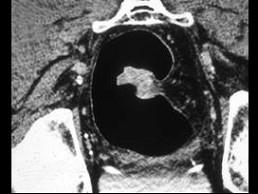

问题 男,56岁,下腹疼痛、大便潜血阳性,结合图像应考虑为 ( )

选项 A、直肠间质瘤 B、直肠淋巴瘤 C、直肠癌 D、直肠腺瘤 E、直肠息肉

答案 C